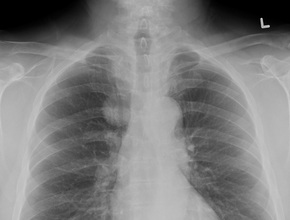

A 75-year-old female patient who presented with exertional dyspnea. You order a chest x-ray (Fig. 1a, b).

Figure 1. PA (a) and lateral chest x-ray (b).

Do you see an abnormality on the PA and lateral views?

The x-ray shows a large well-circumscribed, non-calcified mass (Fig. 2a) overlying the inferior left side of the chest. There are tubular elongated structures that appear to emulate from the mass coursing towards the left hilum. On first glance you may think that this mass is associated with the left breast. However, when you look on the lateral x-ray (Fig. 2b) you can see that this mass (arrows) lies posterior and by process of elimination can only lie within the left lung.

Figure 2. a, PA chest x-ray. A well-circumscribed, non-calcified mass (arrow) lies within the left lung.

Tubular elongated structures (arrowheads) are seen extending from the mass coursing towards the left hilum, b, lateral Chest X-ray. A well-circumscribed, non-calcified mass (arrows) lies posteriorly within

the left lung.